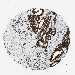

PANCREATIC CANCER - Protein expressioni

A mouse-over function shows sample information and annotation data. Click on an image to view it in a full screen mode. Samples can be filtered based on level of antibody staining by selecting one or several of the following categories: high, medium, low and not detected. The assay and annotation is described here.

Note that samples used for immunohistochemistry by the Human Protein Atlas do not correspond to samples in the TCGA dataset.

Antibody stainingi

Antibody staining in the annotated cell types in the current human tissue is reported as not detected, low, medium, or high, based on conventional immunohistochemistry profiling in selected tissues. This score is based on the combination of the staining intensity and fraction of stained cells.

Each image is clickable and will lead to virtual microscopy that enables deeper exploration of all samples and also displays staining intensity scores, fraction scores and subcellular localization as well as patient and tissue information for each sample.

Antibody HPA010592

Antibody CAB002506

Antibody CAB079994

Adenocarcinoma, NOS

Adenocarcinoma, metastatic, NOS